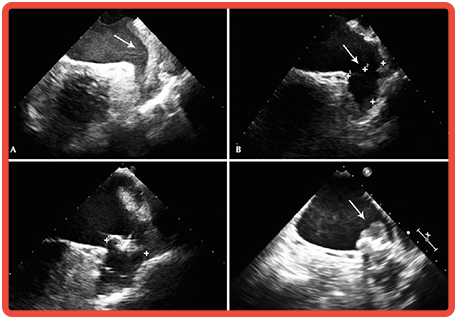

8 - Ecocardiograma Transtorácica Adulto 2D

Avaliar a anatomia e funcionamento do coração.

COMO É FEITO![]()

O exame é realizado pelo especialista titulado em ecocardiografia. Neste procedimento o médico utiliza um aparelho específico de ultrassonografia na região do tórax do paciente, para examinar o coração e os vasos sanguíneos próximos, para obter imagens de múltiplos planos.

INDICAÇÕES![]()

É indicado para detectar e quantificar as doenças cardíacas e dos grandes vasos relacionados ao coração. Analisar quantitativamente a função cardíaca, o fluxo sanguíneo através das valvas e tamanhos das cavidades. Avaliação da sincronia cardíaca.